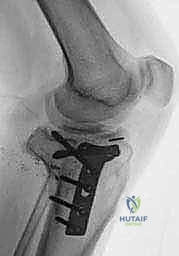

الدليل المصور: خطوات جراحة استبدال مفصل الركبة الكلي بالإسمنت خطوة بخطوة

تُعد هذه الجراحة عملاً فنياً هندسياً ودقيقاً، يتطلب مهارة جراحية استثنائية. بفضل تقنيات الجراحة المجهرية واستخدام أحدث الأدوات، يضمن الأستاذ الدكتور محمد هطيف دقة متناهية في كل خطوة. نستعرض هنا توثيقاً دقيقاً من داخل غرفة العمليات (Intraoperative Steps):

2. تحضير عظم الفخذ (Femoral Preparation)

باستخدام أدوات قياس وقطع متطورة جداً، يتم إزالة الطبقة الرقيقة التالفة من أسفل عظم الفخذ وتشكيل العظم ليتطابق تماماً مع الجزء المعدني من المفصل الصناعي.

3. تحضير عظم قصبة الساق (Tibial Preparation)

بنفس مستوى الدقة، يتم إزالة السطح التالف من أعلى قصبة الساق، وتسويته ليكون قاعدة صلبة ومستوية تماماً لاستقبال الجزء السفلي من المفصل.